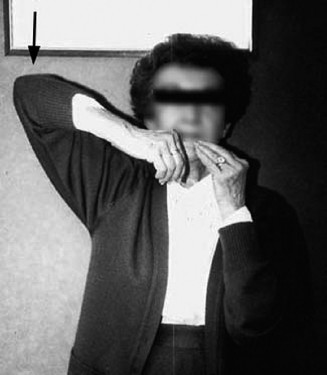

The belly press test (Answer A) and lift off test (Answer D) are used to evaluate for subscapularis pathology (Figs. 2–3 and 2–4). The hornblower test (Answer B) assesses the teres minor (Fig. 2–2). The external rotation lag test (Answer E) evaluates the infraspinatus.

Figure 2–2_Positive hornblower’s sign. (From Kuzel BR, Grindel S, Papandrea R, Ziegler D. Fatty infiltration and rotator cuff atrophy. _J Am Acad Orthop Surg. 2013;21(10):613–623.)